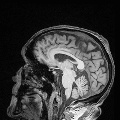

Multi-modality (or multi-channel) imaging is becoming increasingly important and more widely available, e.g. hyperspectral imaging in remote sensing, spectral CT in material sciences as well as multi-contrast MRI and PET-MR in medicine. Research in the last decades resulted in a plethora of mathematical methods to combine data from several modalities. State-of-the-art methods, often formulated as variational regularization, have shown to significantly improve image reconstruction both quantitatively and qualitatively. Almost all of these models rely on the assumption that the modalities are perfectly registered, which is not the case in most real world applications. We propose a variational framework which jointly performs reconstruction and registration, thereby overcoming this hurdle. Numerical results on simulated and real data show the potential of the proposed strategy for various applications in multi-contrast MRI, PET-MR, and hyperspectral imaging: typical misalignments between modalities such as rotations, translations, zooms can be effectively corrected during the reconstruction process. Therefore the proposed framework allows the robust exploitation of shared information across multiple modalities under real conditions.